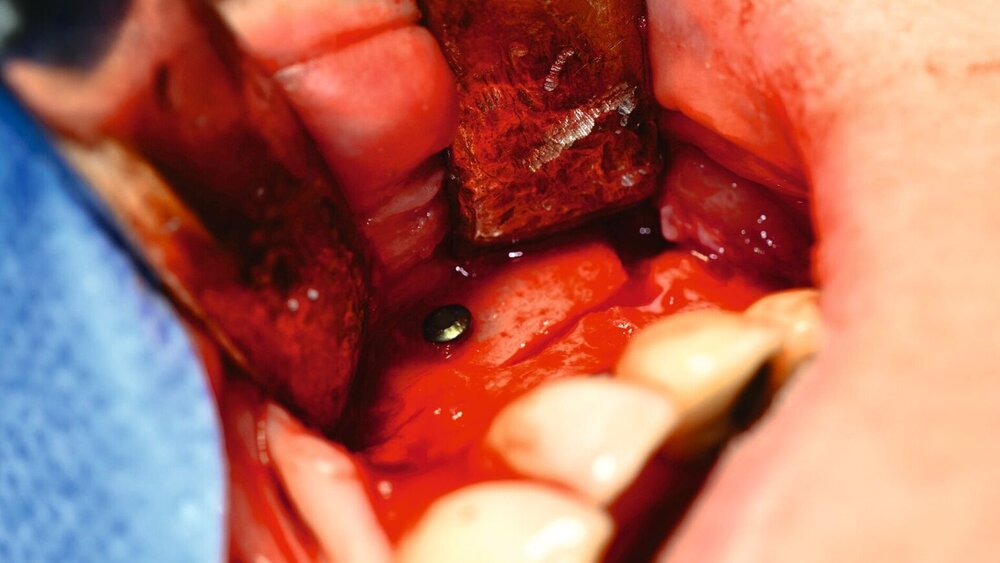

Eine 35-jährige Patientin stellte sich immer wieder mit rezidivierenden Schmerzen der linken Gesichtshälfte bei mehreren Ärzten vor. Die Beschwerden bestanden seit Jahren. Schon im Vorfeld waren mehrfach bei chronischer Sinusitis eine Kieferhöhlenrevision sowie eine Infundibulotomie linksseitig erfolgt. Regelmäßig kam es zu erneuten eitrigen Entzündungen. Die fraglichen Fokuszähne des zweiten Quadranten 24–27 waren vor einigen Jahren entfernt worden (Abbildung 1). 2017 war eine komplikationslose implantologisch-prothetische Versorgung der Freiendsituation erfolgt (Abbildungen 2 und 3).